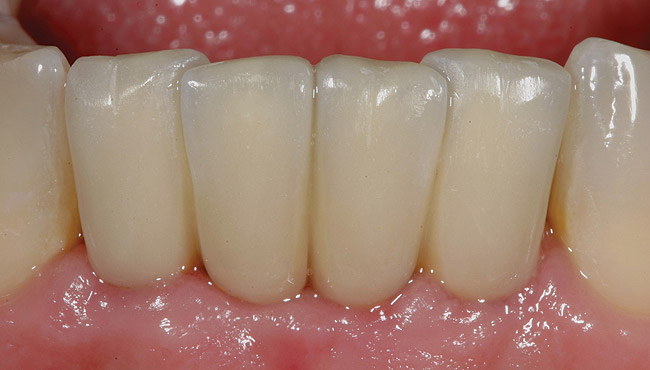

Figure 1  Preoperative clinical condition.

Figure 1